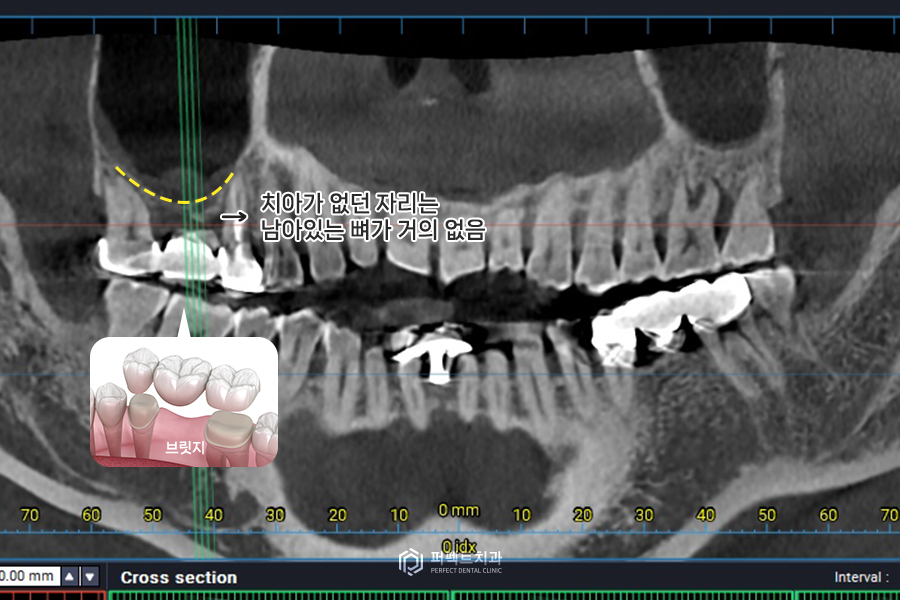

통증이 있는 치아 부위는 상악동에 염증이 있고, 치아가 없던 자리(브릿지를 했던 자리)는 뼈가 거의 없는 상태입니다. 이 사진으로만 봐도 1~2mm정도 있을까 하는 정도인데 임플란트를 편안하게 심으려면 적어도 10mm길이의 공간이 있는 것이 좋습니다.

1~2mm정도의 공간으로는 임플란트를 심기 힘들기 때문에 상악동막을 들어올려서, 그 부분에 뼈를 채워넣는 상악동거상술 뼈이식을 한 경우라고 보시면 될 것 같습니다.

수술 하기 전 CT사진을 보시면 아까 말씀드렸듯이 뼈가 없는 부분은 거의 퇴화해서 둘러싸고 있는 치조골이 거의 없습니다. 사진상 보이는 하얀 부분이 뼈인데, 실제로 약 1mm정도의 뼈가 있고, 위에 표시된 부분은 염증, 검게 비어있는 부분이 상악동입니다.